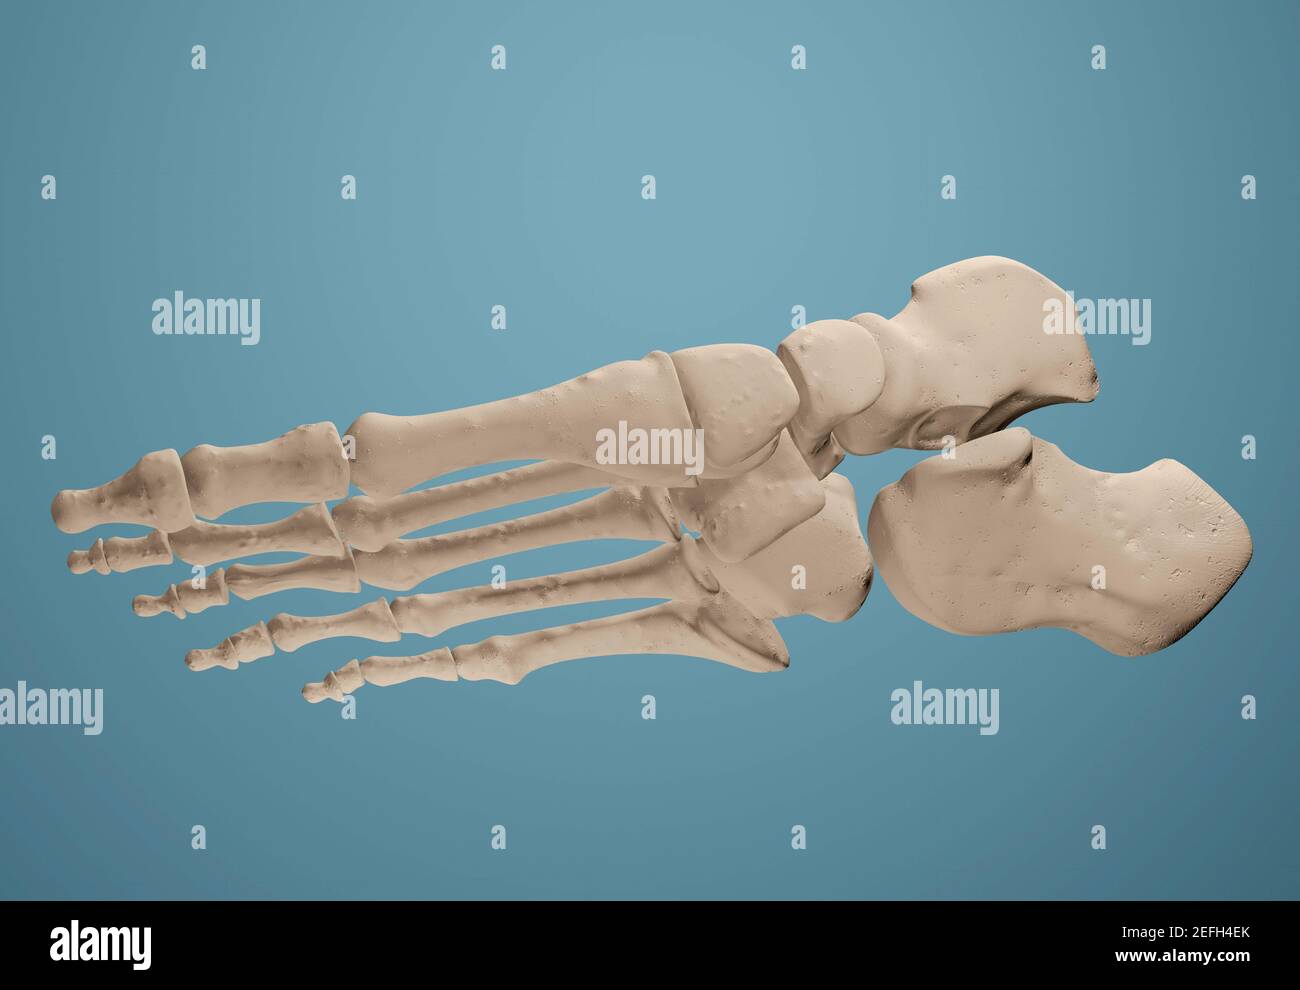

RF2R3WKY1–Illustration médicale des principales parties des os du pied en vue latérale, avec annotations.

RF2EFH4NT–Affiche prête pour la salle de classe montrant les os du pied dans des vues anatomiques et éclatées.